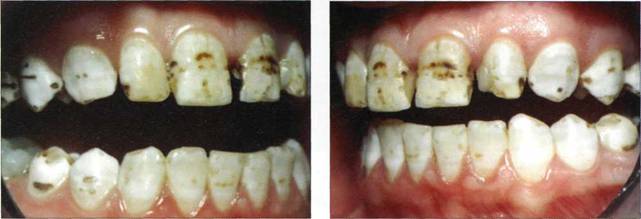

Клинический пример 21

Пациентке 28 лет. Тортоаномалия зубов верхней челюсти. Произведена реконструкция верхних резцов материалами семейства "Filtek", фирмы "3M-ESPE".

Рис. 782. Исходная клиническая ситуация

Рис. 783. Конечный результат